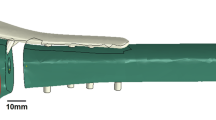

In addition, the pediatric hip locking plate (LCP Pediatric Plate System, DePuy Synthes company, USA), used in this 3D virtual patient model, was measured using a digital caliper and converted to a finite element model, as shown in Fig. 1b. The screw holes in this pediatric hip locking plate were set to a diameter of 5.0 mm, and the location and number of screw holes were set to three in the direction of the femoral head and three in the direction of the femur. Based on the product specifications, the diameter and length of the screws were set to 5.0 mm and 23–45 mm, respectively. After selecting the positions of the screws inserted into the femoral head, the screws inserted in the direction of the femur were positioned based on the groove of the pediatric hip locking plate, and they were vertically fixed with the pediatric hip locking plate. Finally, ABAQUS (Version 2022, Dassault Systemes, Simulia, USA) finite element program was used to perform three-dimensional FEA, with a total of 1,496,941 solid elements in the finite element model. The femur and pediatric hip locking plate were composed of C3D4 element types in the form of tetrahedrons of sizes 0.2 and 0.5 mm, respectively, whereas the screw was composed of C3D8R element types in the form of hexahedrons of size 0.3 mm.